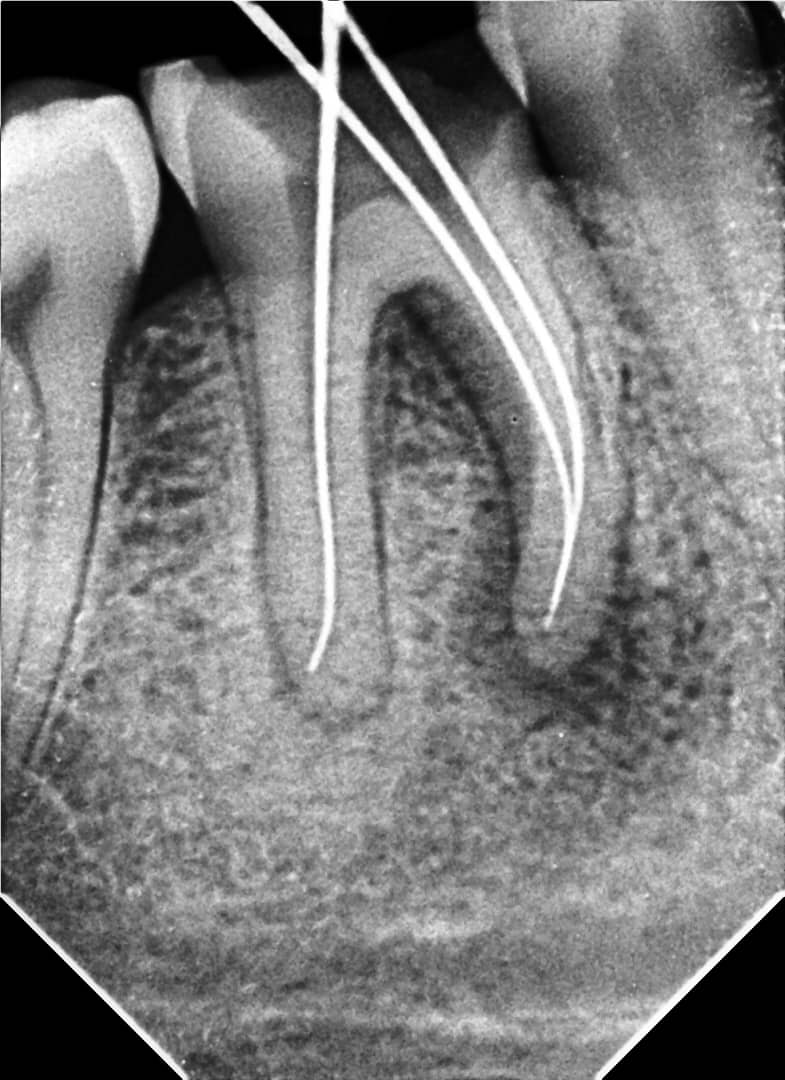

Treatment:

- Mechanical instrumentation using SUPER FILES III rotary files up to size F3

- Irrigation with 3.25% sodium hypochlorite (NaOCl)